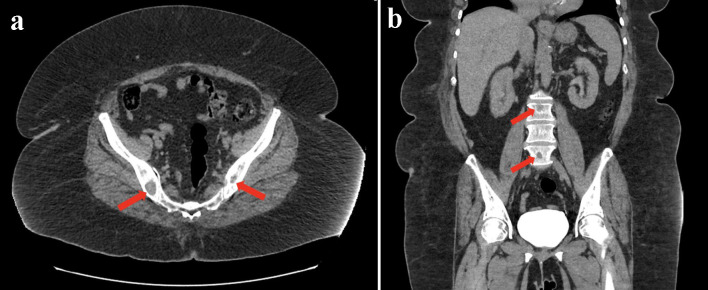

Ribociclib是一种细胞周期蛋白依赖性激酶4/6 (CDK4/6)抑制剂,广泛用于治疗激素受体阳性(HR+)、人表皮生长因子受体2 (HER2)阴性的转移性乳腺癌。虽然肝毒性是一种公认的不良反应,但核素环lib引起的严重肝损伤并组织学证实为大面积下肝坏死的病例仍然很少见。我们描述了一例绝经后妇女,新诊断为IV期HR+/ her2阴性浸润性小叶癌,在开始使用核环昔布和阿那曲唑8周后发生急性肝细胞损伤。患者表现为疲劳、黄疸、尿色深,转氨酶明显升高(丙氨酸转氨酶1825 U/L,天冬氨酸转氨酶1536 U/L)和高胆红素血症。彻底的检查排除了病毒、自身免疫和梗阻性肝胆原因。肝活检显示融合性小叶中心坏死,无纤维化或明显炎症。因果关系评估的r因子为20.73,Roussel Uclaf因果关系评估方法得分为10(极可能),Naranjo得分为7(很可能)。停用Ribociclib,开始静脉注射n -乙酰半胱氨酸(NAC),导致肝酶逐渐正常化。患者单用阿那曲唑维持治疗,随访13个月无肝损伤复发,病情稳定。本病例强调了核素环尼诱导严重肝细胞损伤的潜力,组织学证据显示为大面积坏死。早期识别和结构化的因果关系评估确保了患者的安全。对于有明显肝毒性的患者,停用核素环尼和不再给药可能是谨慎的。此外,在核糖素停药后仍出现持续性转氨炎的病例中,在管理中考虑NAC是很重要的。

Ribociclib, a cyclin-dependent kinase 4/6 (CDK4/6) inhibitor, is widely used in the treatment of hormone receptor-positive (HR+), human epidermal growth factor receptor 2 (HER2)-negative metastatic breast cancer. Although hepatotoxicity is a recognized adverse effect, severe cases of ribociclib-induced liver injury with histologic confirmation of submassive hepatic necrosis remain rare. We describe a case of a postmenopausal woman with newly diagnosed stage IV HR+/HER2-negative invasive lobular carcinoma who developed acute hepatocellular injury 8 weeks after initiating ribociclib and anastrozole. The patient presented with fatigue, jaundice, and dark urine, and was found to have markedly elevated transaminases (alanine aminotransferase 1,825 U/L; aspartate aminotransferase 1,536 U/L) and hyperbilirubinemia. A thorough workup excluded viral, autoimmune, and obstructive hepatobiliary causes. Liver biopsy demonstrated confluent centrilobular necrosis without fibrosis or significant inflammation. Causality assessments yielded an R-factor of 20.73, a Roussel Uclaf Causality Assessment Method score of 10 (highly probable), and a Naranjo score of 7 (probable). Ribociclib was discontinued and intravenous N-acetylcysteine (NAC) initiated, leading to gradual normalization of liver enzymes. The patient was maintained on anastrozole alone, with no recurrence of liver injury and stable disease at 13-month follow-up. This case highlights the potential for ribociclib to induce severe hepatocellular injury with histologic evidence of submassive necrosis. Early recognition and structured causality assessment ensures patient safety. In patients with significant hepatotoxicity, discontinuation of ribociclib and non-rechallenge may be prudent. Furthermore, consideration of NAC in management is important in cases demonstrating persistent transaminitis despite ribociclib discontinuation.